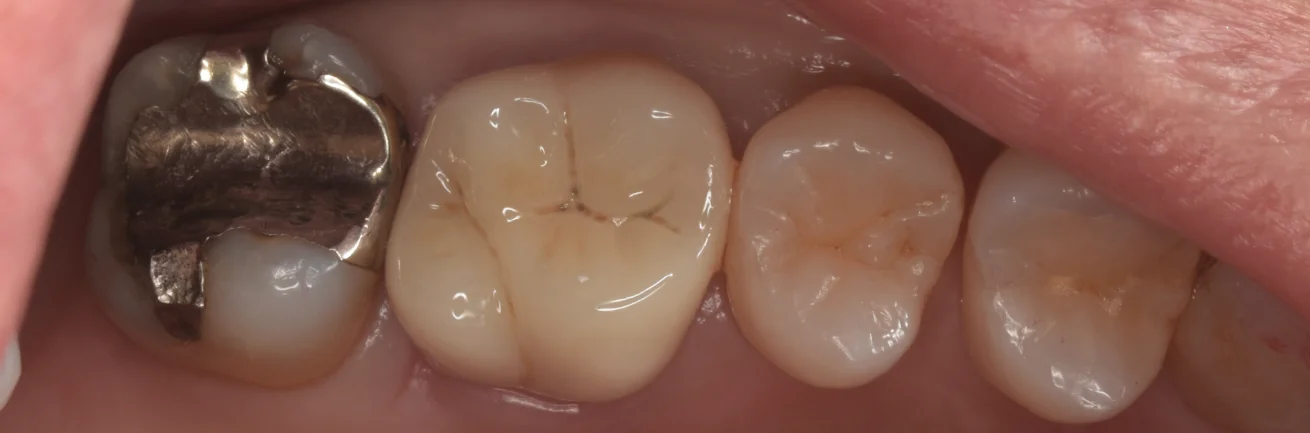

これがSet直前の歯の状態です。

外側性修復(歯の全周を削る所謂被せ物)の場合は全体的に歯が一回り小さくなってしまうため、上記した通り一気に歯が少なくなってしまいます。。。

ただ治療を繰り返すことで必ずこうなってしまいますのでやはり1回1回の治療がどれだけ長持ちするかは非常に大事ですね。

そしてSetした写真がこちらです。

次は側面からの写真です。

Set前に適切な仮歯を入れることで歯茎の形を綺麗にしたり、Set時の乾燥を容易にしたりすることができます。

側面からのSet時の写真です。

手前の歯の隙間に比べると綺麗に歯茎の形ができており、隙間が埋まっているのがわかるかと思います。